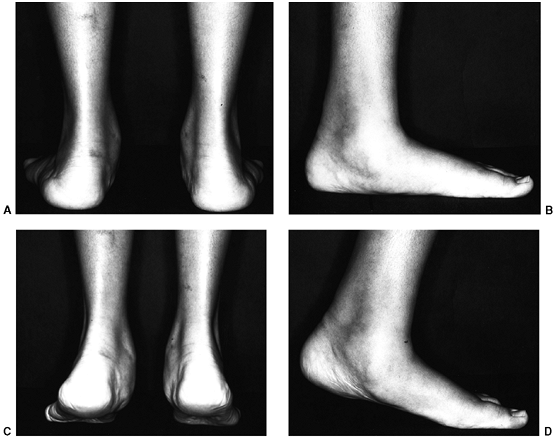

![]() |

|

Figure 30.14 A: Valgus deformity of the hindfoot is a complication of clubfoot management resulting in weak push-off and pain. B: Computed tomography (CT) scan is used to evaluate the deformity and the subtalar joint.

for rigid forefoot supination that may drive the hindfoot deformity.

Also evaluate the muscle strength in all groups, including the

posterior tibial muscles. With the patient rising on the toes, look for

evidence of subtalar motion, with normal mechanics representing a

slight tip of the hindfoot into varus with plantar flexion. Standing

anteroposterior and lateral radiographs of the foot underestimate the

deformity of hindfoot valgus in general. A CT scan will allow

evaluation of the subtalar joint as well as the alignment of the

hindfoot deformity. Also, be aware that valgus may result from the

tilting of the distal tibial articular surface.

calcaneal translational osteotomy as well as calcaneal lengthening, and

finally, subtalar arthrodesis. In severe cases, triple arthrodesis may

be necessary. In a calcaneal slide osteotomy, the tuberosity of the

calcaneus is shifted medially, generally from the lateral approach,

with the calcaneal osteotomy just posterior to the posterior facet of

the subtalar joint. In order for the procedure to work, a competent

subtalar joint must be present and is best evaluated using a CT scan (Fig. 30.14B).

The axis of alignment of the foot in weight-bearing may be corrected

with a translational osteotomy, and the pull of the gastrocsoleus

complex may be shifted into proper alignment with the tibial talar

joint. The calcaneal slide osteotomy will not affect the midfoot and

forefoot deformity. It also will not affect the longitudinal arch of

the foot nor the talonavicular relation.